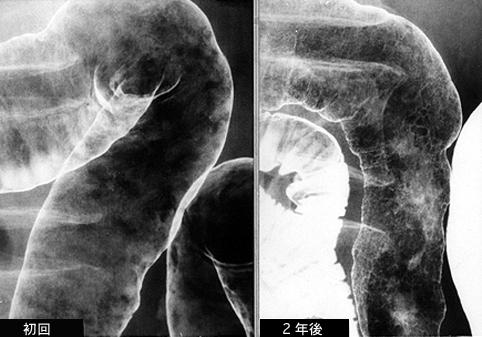

症例提示(所在地,施設名等): 東京都・ 国立がんセンター中央病院と九州がんセンターの共同作成

症例登録日 2005/03/30

疾患(病理主体)の分類炎症性・潰瘍性疾患/消化管アミロイドーシス

部位(臓器別)大腸/横行

検査方法X-P